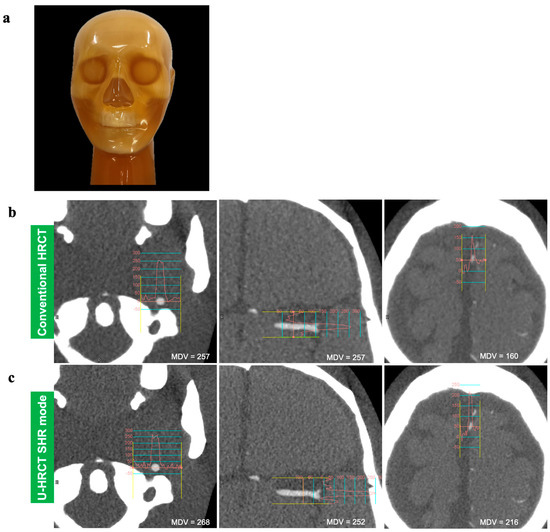

3.1.2. Arterial Density Assessment

Comparisons of the maximum density values of the mock arteries between conventional HRCT and two scan modes of U-HRCT are shown in Table 1 and Figure 1. For the proximal artery, the maximum density of the SHR mode was significantly higher than that of conventional HRCT (p < 0.01). For the peripheral artery, the maximum density of the SHR mode was significantly higher than that of conventional HRCT or the HR mode (p < 0.01).

Figure 1. The actual appearance of a commercially available head-neck CT phantom (a). The density curves of the proximal, intermediate, and peripheral parts of the mock artery on axial images of conventional HRCT (b) and U-HRCT (SHR mode) (c). Note that the maximum density value (MDV) is similar at the intermediate part, while the MDVs of the proximal and peripheral parts of U-HRCT (SHR mode) are higher (268 HU and 216 HU) than those of conventional HRCT (216 HU and160 HU).